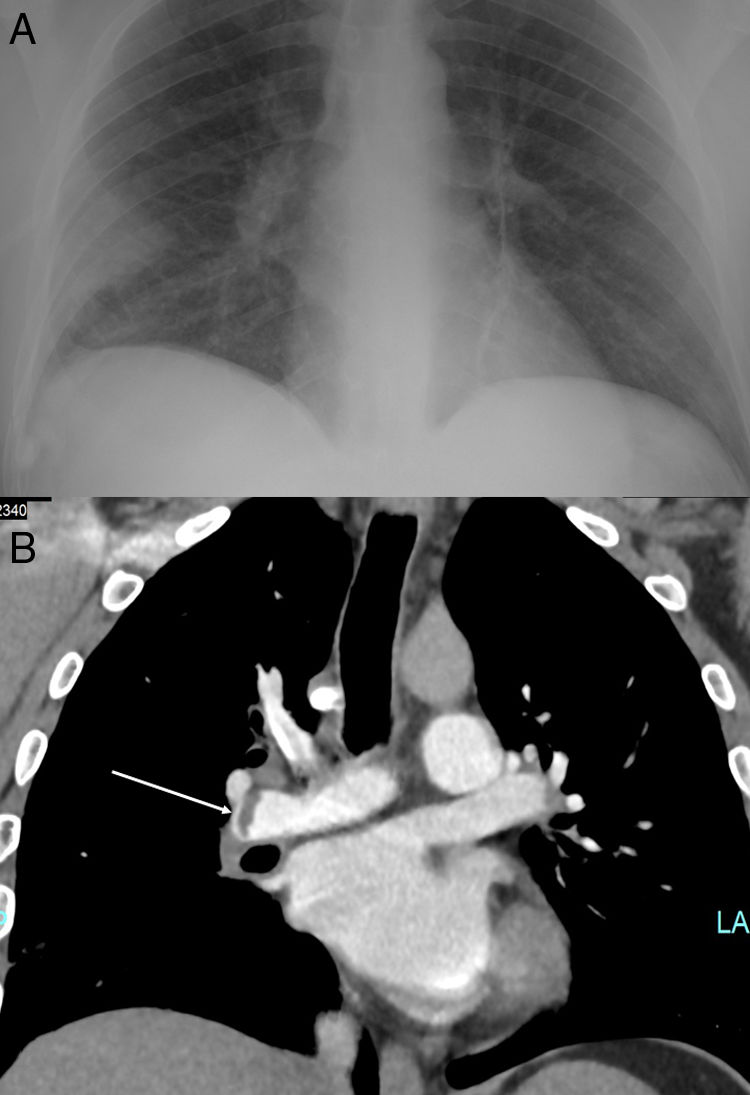

Dyspnea and pleuritic chest pain during the COVID19 pandemic Pleuritic Chest Pain In Covid 19 It can cause chest pain or a burning sensation in your lungs. The centers for disease control and prevention (cdc) lists. However, there have been reports of persistent severe illness with weeks of fevers. The coronavirus can attack your lungs and heart. The most common symptoms were dyspnea (43%), fatigue (53%), joint pain and chest pain. Cardiologists urge patients who. Pleuritic Chest Pain In Covid 19.

EPICARDIAL FAT NECROSISA RARE DIFFERENTIAL DIAGNOSIS OF CHEST PAIN IN Pleuritic Chest Pain In Covid 19 It can cause chest pain or a burning sensation in your lungs. Pleurisy is a painful lung condition that makes it hard to breathe. The centers for disease control and prevention (cdc) lists. However, there have been reports of persistent severe illness with weeks of fevers. The coronavirus can attack your lungs and heart. The most common symptoms were dyspnea. Pleuritic Chest Pain In Covid 19.